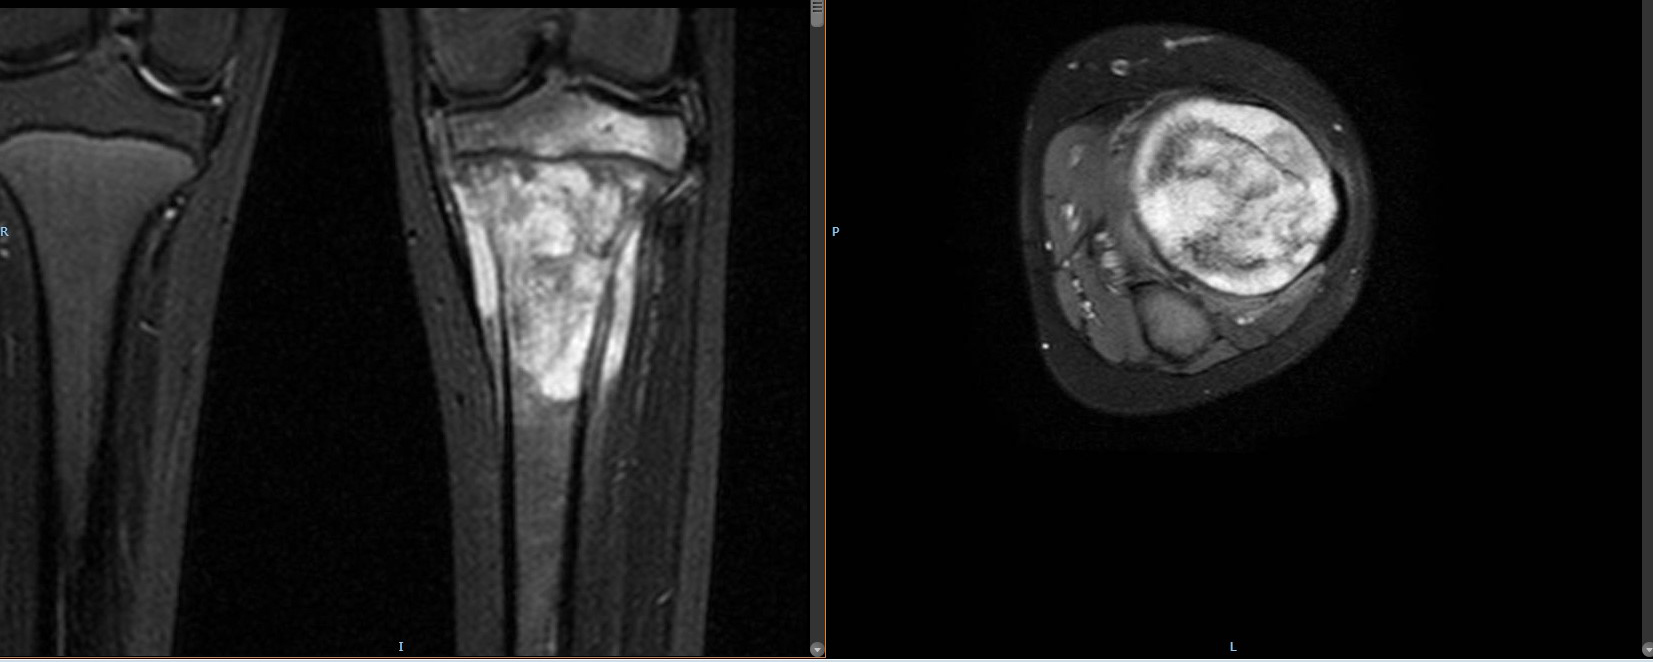

- Ressonância Magnética (RM): Fornece detalhes sobre a extensão do tumor e sua relação com os tecidos moles ao redor.

- Osteossarcoma: O tipo mais comum de sarcoma ósseo, que geralmente afeta os ossos longos, como o fêmur e a tíbia, principalmente em adolescentes e adultos jovens.

- Sarcoma de Ewing: Afeta ossos e tecidos moles, geralmente em crianças e jovens adultos. Frequentemente acomete os ossos da pelve, pernas e braços.

- Condrossarcoma: Tumor que surge na cartilagem, geralmente afetando ossos das extremidades.